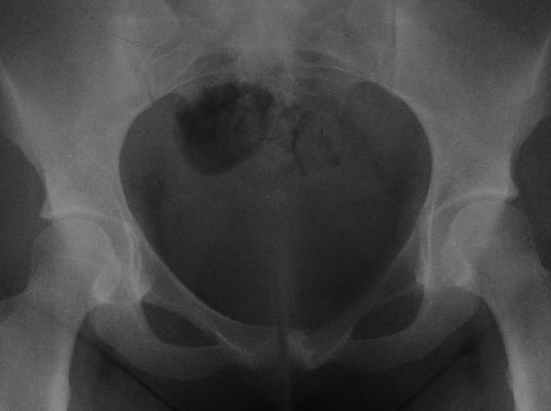

пациентка 20 лет, в сентябре 2005 года почувствовала боли в паху. На снимках заподозрили остеомиелит, лечили антибиотиками без эффекта. К онкологу попала в январе2006. Биопсия в марте 2006 - остеобластокластома. Местные онкологи от операции отказываются.

Вопрос с планом лечения (надо ли замещать деффект и чем) и где оперироваться (опыт подобных операций).В приложении рентгенограммы в динамике (2005 сентябрь, декабрь, 2006 апрель).